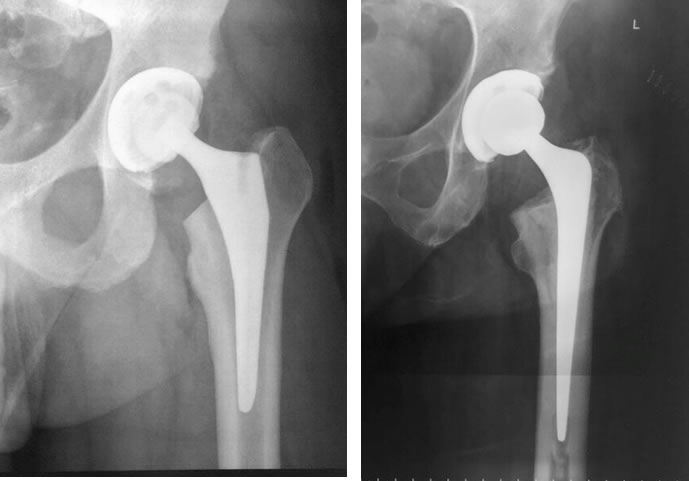

El Reemplazo total de cadera (artroplastía de cadera) consiste en la sustitución de la región superior del fémur y del acetábulo por un implante protésico. El objetivo del tratamiento es la disminución de dolor y recuperar la funcionalidad de la articulación

Los estudios por imágenes son complementarios a la revisación médica. Las radiografías comparativas de ambas caderas, y eventualmente una tomografía computada o resonancia magnética nuclear, nos permiten analizar la articulación con los datos obtenidos en la revisación, así como también la planificación adecuada para un eventual procedimiento